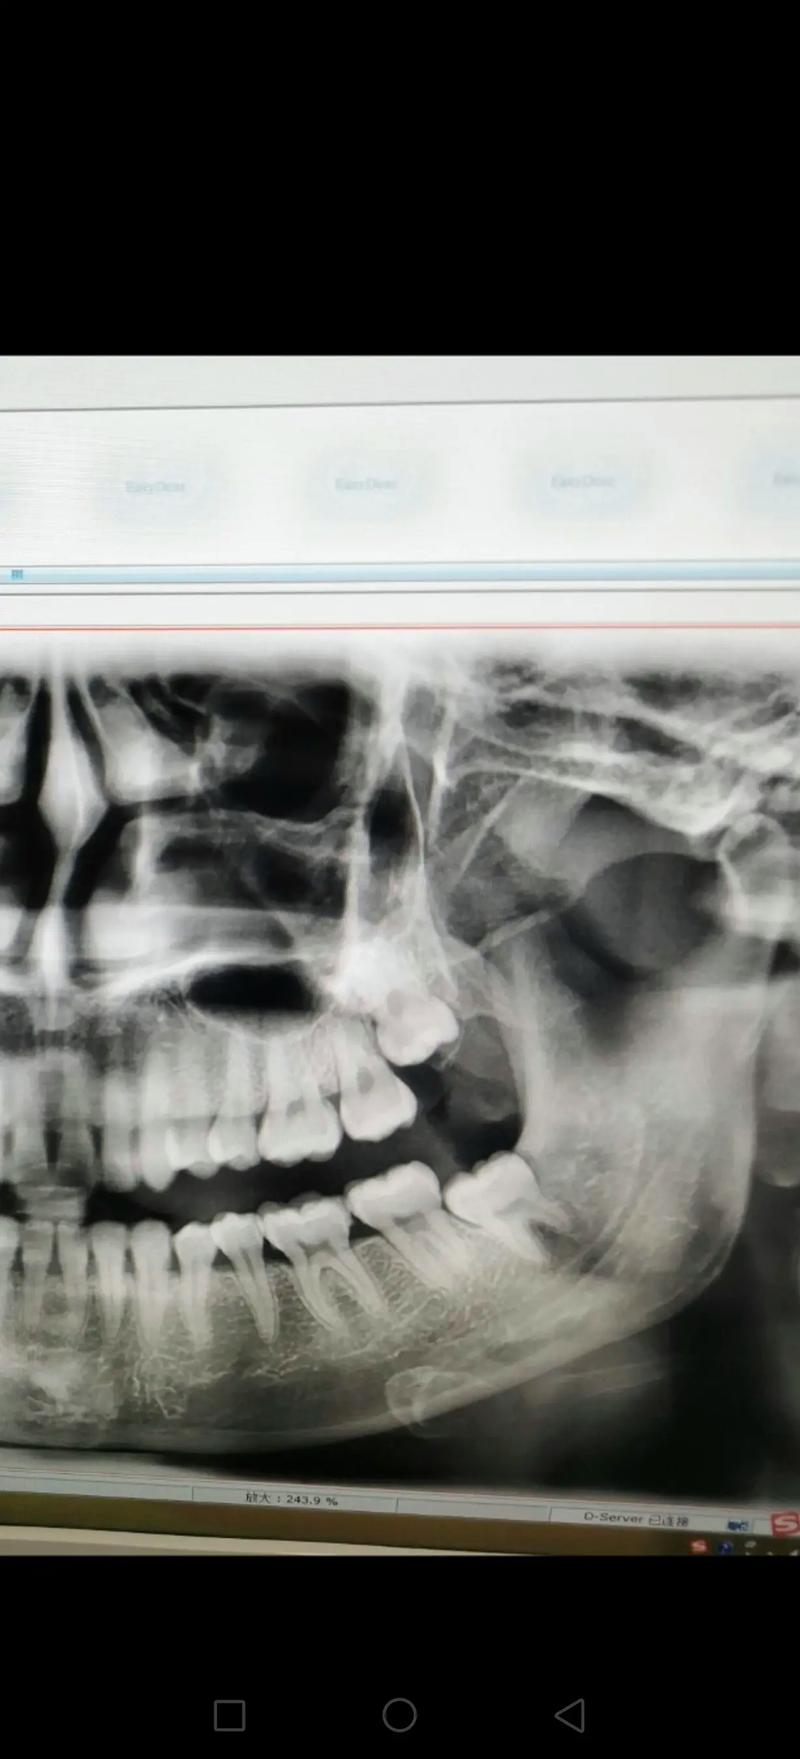

(图片来源网络,侵删)

全景片是二维的“概览图”,适合初步检查;CT是三维的“精细模型”,适合复杂诊断和手术规划。